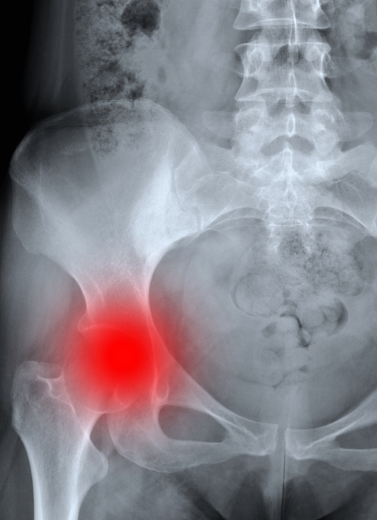

Arthritis and rheumatologic diseases can severely aect your quality of life with persistent pain, swelling, and limited movement. At our Rheumatology & Arthritis Department, Dr. Anand Bhushan oers comprehensive diagnosis and tailored treatments that control symptoms, slow disease progression, and improve joint function.

Osteoporosis-related Fractures